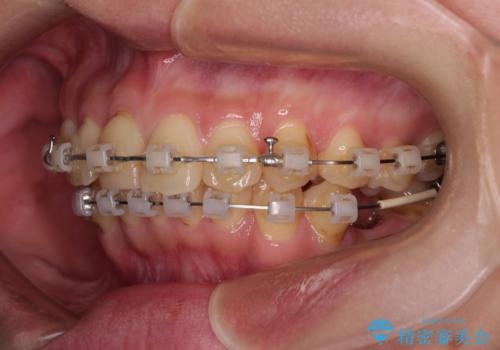

デコボコと乳歯の欠損 ワイヤー矯正とインプラント補綴治療

- 矯正装置

- クリアブラケット

- 全体的なデコボコと左下乳歯部の欠損を気にして来院された患者様です。

乳歯が抜け落ちた後の後続永久歯が欠損しているため、スペースが残っておりました。

口元の突出感を気にしているのであれば欠損スペースを利用して抜歯矯正を行うことも可能ですが、横顔の印象はスッキリとしている状態であったため、矯正治療でスペースを閉じきることは不可能と判断し、インプラントによる補綴治療を行うこととしました。